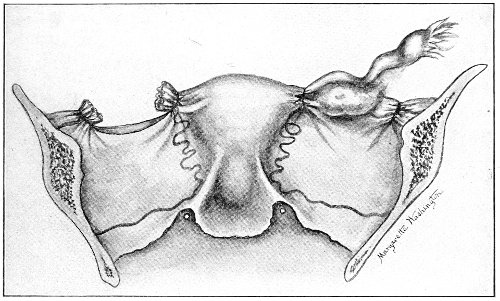

An accurate knowledge of the anatomy and mechanism of the female perineum is essential to an understanding of the nature and treatment of injuries to this structure. The anatomical structures lying between the anus behind and the symphysis pubis in front are those that most directly interest the gynecologist. Proceeding from 57 below upward, we find the following structures lying in superimposed planes: the skin, the superficial fascia, the deep layer of the superficial fascia, the transversus perinæi and the sphincter vaginæ muscles, the anterior layer of the triangular ligament, the posterior layer of the triangular ligament, the levator ani muscle (Fig. 19).

The vagina passes through these structures. They surround and support the ostium vaginæ as the fascia and muscles surround and support the opening of the rectum or the anus. The muscles and fasciæ are attached in the median line between the anus and the vagina, and therefore this part of the body, which is called the perineum, is supported or maintained in its 58 proper position by these various structures. The transversus perinæi arises from the ramus of the ischium and is inserted in the perineum. The bulbo-cavernosus, or sphincter vaginæ, arises in the perineum and is inserted in and about the clitoris. The inner fibers of the levator ani arise from the symphysis pubis and are inserted in the perineum and the lower part of the vagina (Fig. 20). When these muscles contract, their action, therefore, is to draw the perineum upward and forward. At the same time the anus is drawn upward and forward, and so also is the posterior margin of the ostium vaginæ and the lower portion of the posterior vaginal wall.

The vagina has no circular sphincter like the anus, but 59 the vaginal month is kept closed by the action of the transversus perinæi, sphincter vaginæ, and levator ani muscles, which draw the perineum forward, and thus keep the posterior vaginal wall in apposition with the anterior wall.

Fig. 21.—Muscular floor of the pelvis seen from above.

This sling of muscles and fascia, which surrounds and supports the opening of the vagina, may readily be felt in the nulliparous woman by introducing the finger in the vagina and pressing backward and outward toward the ischio-rectal fossa. We then feel plainly, immediately within the ostium vaginæ, a firm resisting band of tissue, apparently about half an inch broad, embracing the posterior portion of the lower vagina. This band is formed by the inner edges of the various muscles and planes of fascia that have been described.

The vagina extends, as a transverse slit in the pelvic floor, upward and backward, approximately in the direction 60 of a line drawn from the ostium vaginæ to the fifth sacral vertebra. It is approximately parallel with the conjugate of the brim, so that when the woman is erect the long axis of the vagina is inclined at an angle of 60° to the horizon. The vagina is not a vertical open tube: it is a slit in the pelvic floor, in health always closed by the accurate apposition of the anterior and posterior walls (Fig. 21). The anterior vaginal wall is about 2½ inches long in a vertical mesial line. The posterior vaginal wall is about 3½ inches long. The vaginal walls are triangular in shape, being broader above than below. The shape of the normal vagina at the pelvic outlet is shown by Fig. 23. The section here shows the vaginal 61 slit of the shape of the letter H. The portions of the slit extending backward and somewhat outward are called the vaginal sulci or furrows. They are directions of diminished resistance in which tears are liable to occur.